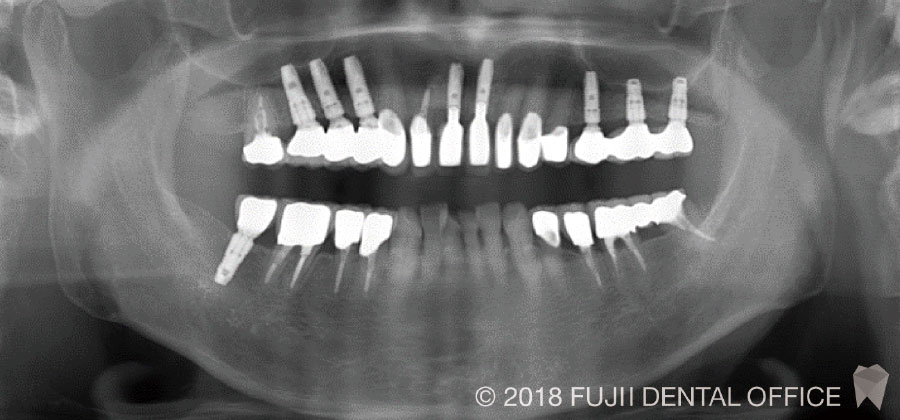

咬合再構成症例

主訴

「審美不良」「咀嚼困難」

目的

不良補綴装置による審美障害・咀嚼障害の回復

治療内容

抜歯+インプラント(抜歯即時埋入、骨造成、ソケットリフト) +審美情報・運動路採得+咬合再構成

副作用・リスク

術後疼痛・腫脹、顎関節症

治療期間

18ヶ月

費用[税抜]

5,700,000円

【内訳】

- インプラント: 350,000円×9本

- 骨造成: 70,000円×2カ所

- ソケットリフト: 50,000×3カ所

- プロビジョナルレストレーション:80,000円×2回

- ジルコニアセラミック冠: 150,000円×14本

目的: 不良補綴装置による審美障害・咀嚼障害の回復

治療内容: 抜歯+インプラント(抜歯即時埋入、骨造成、ソケットリフト) +審美情報・運動路採得+咬合再構成

副作用・リスク: 術後疼痛・腫脹、顎関節症

治療期間: 18カ月

費用[税抜]: 5,700,000円

【内訳】 ・インプラント: 350,000円×9本

・骨造成: 70,000円×2カ所

・ソケットリフト: 50,000×3カ所

・プロビジョナルレストレーション: 80,000円×2回

・ジルコニアセラミック冠: 150,000円×14本